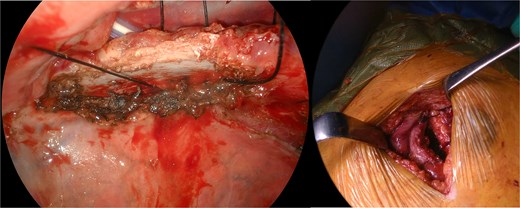

The patient underwent anterior thoracotomy at the site of the hernia, followed by scar resection of the previous incision. Additionally, a 12-mm port was placed at the sixth ICS to facilitate the observation of the thoracic cavity. The hernial defect was repaired exclusively with four stitches of size one nonabsorbable silk suture placed across the ICS between the fourth and fifth ribs, forming the hernial orifice (Fig. 3). Prior to suturing, the adhesion between the right upper lobe and fourth rib was meticulously dissected as extensively as possible. Resection of the herniated lung tissue was not required.

Intraoperative view of rib approximation using nonabsorbable sutures.

The wound was closed in separate layers, including the closure of the pectoralis muscles, deep dermal layer, and subcuticular layer, using running absorbable sutures (Fig. 4). A chest drain was then placed. No recurrence of the lung hernia was observed during the 6-month follow-up period.

Chest drain placed through the port incision following the repair.